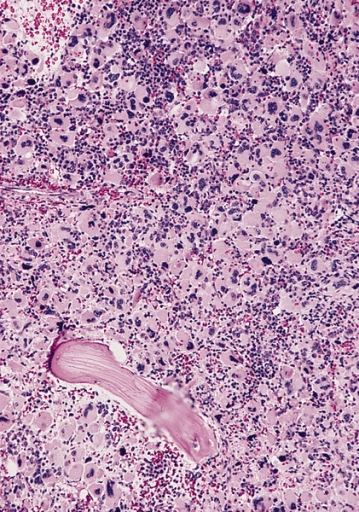

Bone marrow sections from a 64-year-old male with pancytopenia.

Tests like Complete blood count, Kidney function test, Liver function test, Electrolyte levels, Vitamin B12 and Folic acid levels are done to find the cause of pancytopenia. Chest X-ray, CT scan and sonograpy of abdomen are done to rule out other causes of pancytopenia. Bone marrow biopsy will help us confirm the cause of pancytopenia. In Aplastic anemia, biopsy shows hypocellular bone marrow i.e. blood cells are less and replaced by fat.